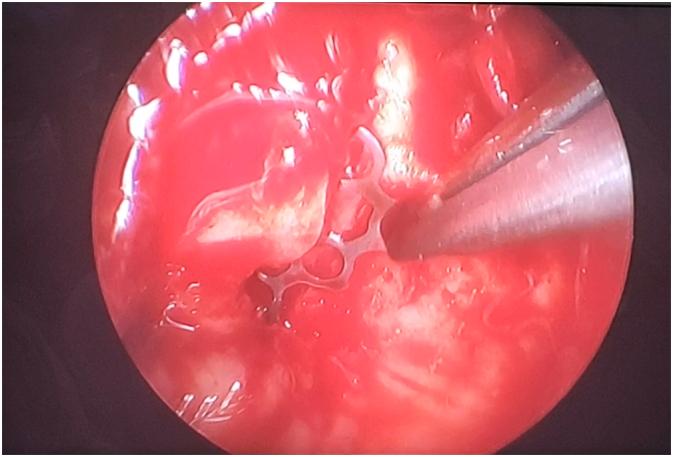

The endoscopy in orbital surgery provides, similar to other surgical fields, the option of combining an extended view of the surgical field with minimally invasive approaches; also allows an excellent functional and esthetic results. Trans-maxillary endoscopy of the orbital floor offers excellent visualization of the posterior bony shelf and confirms that the implant rests securely in place.

In more than 40% of all the facial fractures parts of the orbital rim or/and the internal orbit are injured with a variety of fracture patterns. Accurate assessment is required in order to correct any bone defects or displacements. The surgical approaches have become more reduced offering better control of orbital pathological processes. Orbital lesions are precisely localized through imaging. Also, the approach decision depends on location, size and vascularization. No consensus exists regarding the timing of the repair, the repair technique and the optimal implant. In this case presentation, the defect on the orbital floor was extended by mobilization of the fragments. A combination of incisions was necessary due to the change in the dimensions of the defects intraoperatively and entrapment of orbital tissue by the placement of an implant.

The endoscopic approaches provide excellent visualization and safe from eyelid complications with no visible scar when secondary open fracture reduction is avoided. Also; the rate of postoperative complications are reduced: optic nerve injury, orbital apex injury.